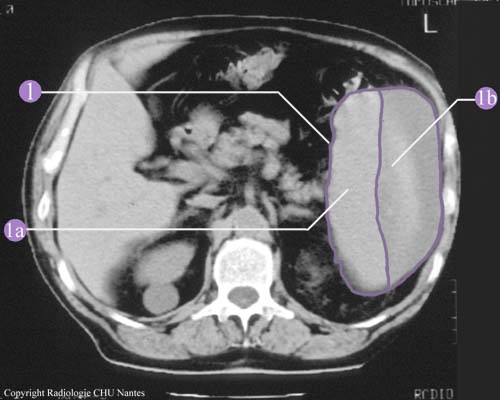

HÉMATOME SOUS-CAPSULAIRE

Examen tomodensitométrique sans injection

1.Rate très augmentée de volume.

1a. Rate déformée par une masse hypodense correspondant à un hématome sous-capsulaire.

1b. Hématome sous-capsulaire : plage hypodense de sang séparant la rate de sa capsule.